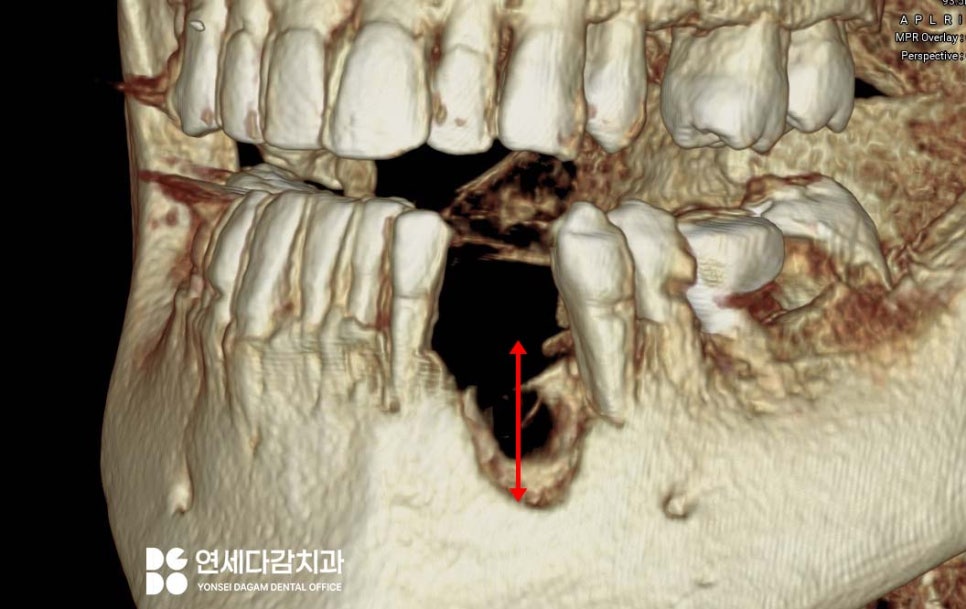

정확한 진단과 치료 계획을 위해

가락시장역 치과 에서

CT를 이용한 3차원적인

구조로 살펴본 결과,

역시나 골소실이 상당히

심한 것을 확인할 수 있었습니다.

이런 경우에는 뼈이식의 성패가

치료 결과를 좌우하는

중요한 요소가 됩니다.

따라서 골이식을 동반한

임플란트 수술 계획을 수립했으며,